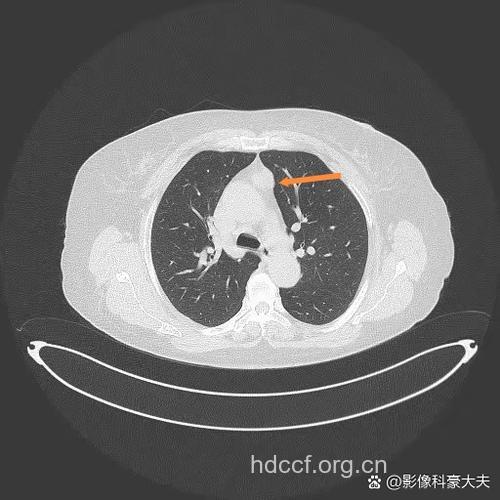

临床表现:20%~40%胸腺瘤在发现时没有症状,仅在查体时偶然发现。1/3的患者有瘤体侵犯或压迫邻近纵隔结构所引起的局部症状,包括咳嗽、胸痛、气短、吞咽困难、声嘶或呼吸道感染,上腔静脉压迫综合征多见于恶性胸腺瘤。30%一50%的胸腺瘤患者合并重症肌无力,但重症肌无力患者仅有15%-20%有胸腺的病变。重症肌无力在女性患者更常见,表现为复视、上睑下垂、肌肉无力和容易疲劳等症状。胸腺切除术后2/3患者重症肌无力症状能够减轻,但常需要数月时间。少数患者可发生低丙种球蛋白血症、单纯红细胞再生障碍、皮质醇增多症以及一些免疫异常如红斑狼疮、多发性肌炎等。